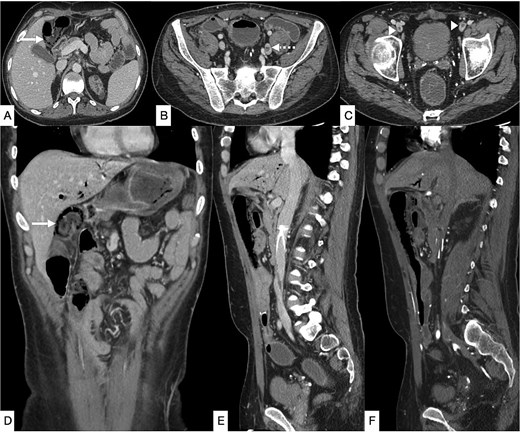

Contrast-enhanced computed tomography (CT) of the abdomen demonstrated long-segment ischemia extending from the transverse to descending colon, characterized by wall thickening, mucosal hypoenhancement, and pericolic fat stranding. A non-occlusive thrombus was noted in the IVC (Fig. 1). Review of prior CT angiography, performed several months earlier for gastrointestinal bleeding, had shown features of colonic angiodysplasia, including mucosal hyperenhancement, early venous filling, and serpiginous submucosal vessels (Fig. 2).

Selected CT angiogram of the abdomen and pelvis in axial (A) and coronal (B) planes showing mild diffuse thickening and mucosal hyper-enhancement of the descending colon, with prominent feeding mesenteric arteries and early draining vein dilation, consistent with angiodysplasia.

Three months later, the patient re-presented with severe right iliac fossa pain radiating to the left abdomen, associated with fever and clinical peritonism. Laboratory evaluation again demonstrated metabolic acidosis, leukocytosis, and elevated inflammatory markers. CT of the abdomen demonstrated pneumatosis intestinalis in the terminal ileum adjacent to the ileocolic anastomosis, together with new thrombi in the left common iliac and bilateral femoral veins (Fig. 3).

Contrast-enhanced CT of the abdomen and pelvis in axial (A–C), coronal (D), and sagittal (E, F) planes showing diffuse pneumatosis intestinalis just proximal to the previous anastomotic site (bold arrow), consistent with bowel ischemia. New thrombi are identified within the left common iliac vein (dashed arrow) and bilateral common femoral veins (arrowhead). Mild residual pneumobilia is present. An IVC filter is seen in situ.